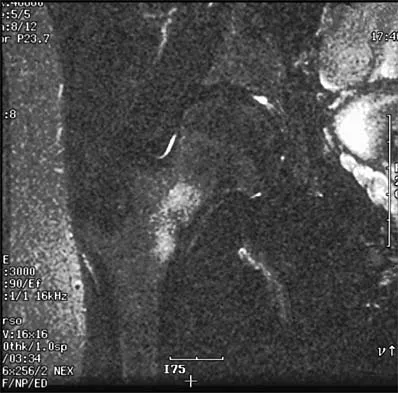

A 30-year-old woman who runs approximately 30 miles a week has had right hip and groin pain for the past 3 weeks. Examination reveals an antalgic gait, limited motion of the right hip, and pain, especially with internal and external rotation. Plain radiographs are normal, and an MRI scan is shown in Figure 21. Management should consist of

Explanation